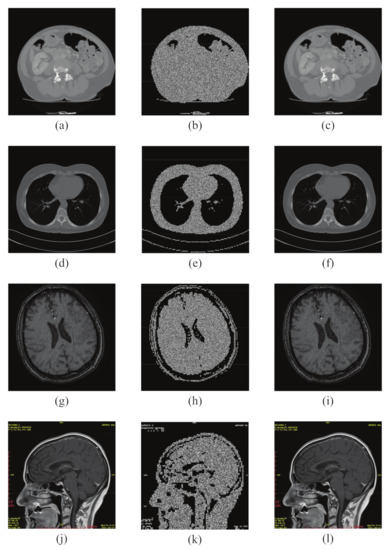

6.1. Simulation Results

4. Selection of Region of Interest Blocks

4.2. Selection of Region of Interest